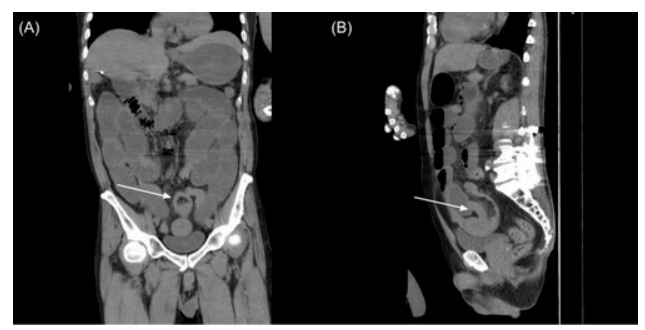

2024年初,患者因出血性枕叶脑转移接受了开颅手术。术后不久,患者出现弥漫性腹痛、腹胀和呕吐等症状。影像学检查显示远端回肠肠套叠(图1)。

图1. 影像学检查显示弥漫性小肠梗阻伴远端回肠套叠(白色箭头),(A)冠状面图像和(B)矢状面图像